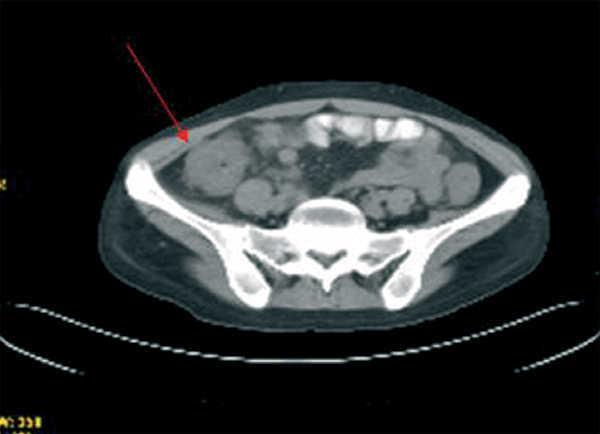

Durante el ingreso, la paciente desarrolló fiebre, dolor abdominal, vómitos y deposiciones diarreicas. Se realizaron coprocultivos, estudio de parásitos, determinación de toxina para Clostridium difficile y antigenemia para citomegalovirus (CMV) en dos ocasiones, que resultaron negativas. Se realizó TC abdominal (figura 1) en la que se observó engrosamiento de la pared del colon con oclusión de la luz desde el ciego hasta la unión recto-sigmoidea compatible con pancolitis difusa. Se solicitó fibrocolonoscopia (figura 2) en la que se objetivó una mucosa edematosa con múltiples lesiones nodulares blandas compatibles con neumatosis coli. En la biopsia de colon se detectaron inclusiones víricas que se confirmaron para CMV por inmunohistoquímica (figura 3). La tercera determinación de antigenemia para CMV fue positiva y el diagnóstico definitivo fue de colitis por CMV.

Figura 1. TC abdominal